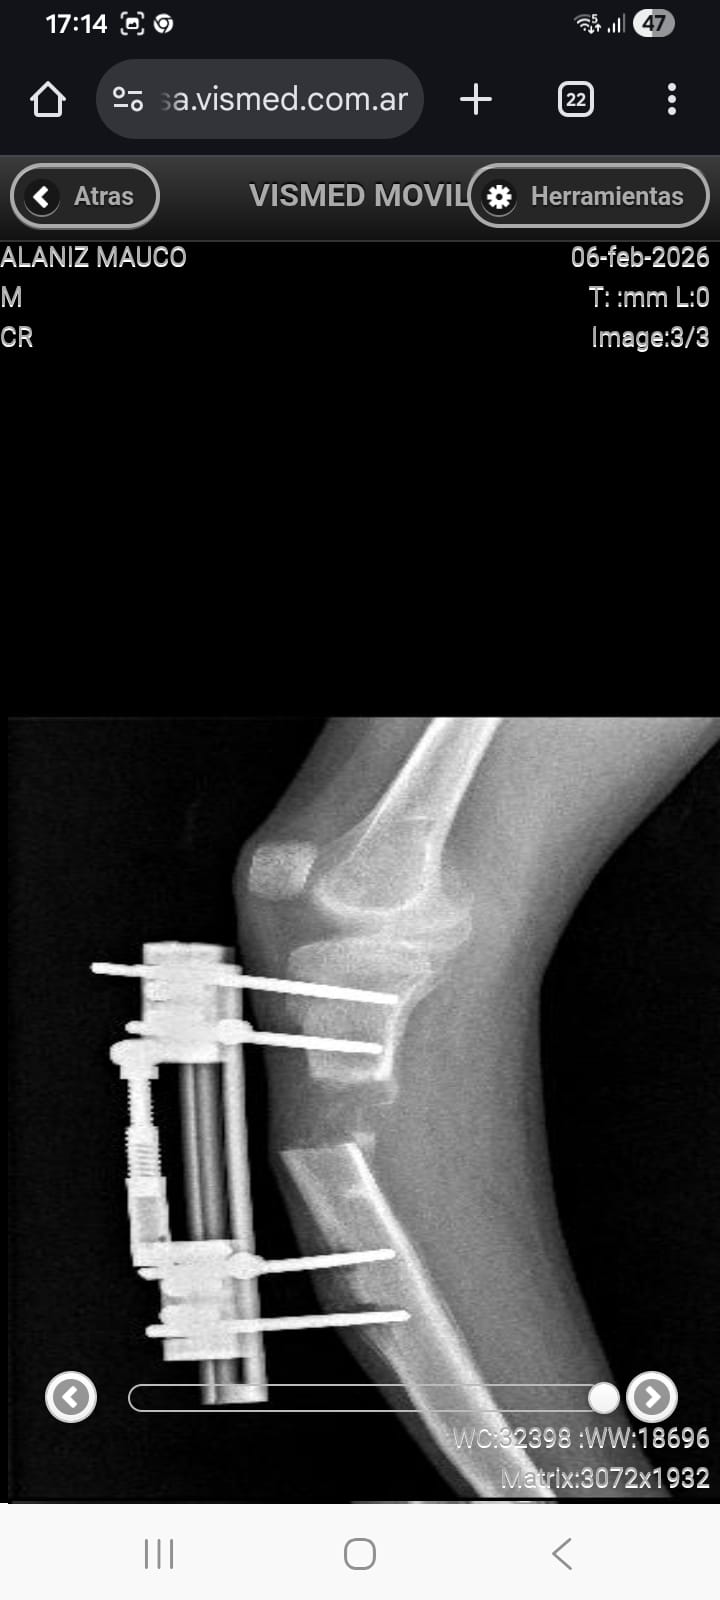

El padre del joven explicó cuál es el problema que afronta su hijo: «Mi hijo nació con una malformación congénita, en donde no tiene el peroné y hace que tenga una diferencia de 7 centímetros con su otra pierna. Ya vamos a llevar 13 operaciones con la de este viernes, y hace un mes y medio lo operamos para hacerle un alargamiento de tibia, pero lamentablemente su hueso se corrió de lugar y es por eso que tiene que ser operado de urgencia para ser corregido y seguir con su tratamiento que lleva más de un año».

Por otro lado, Alfredo manifestó que todas las operaciones de su hijo son ambulatorias, por lo que se encuentra con internación domiciliaria y la intervención quirúrgica se realizará en el Centro Médico Tótem de San Martín. Además, añadió: «Tenemos que pagar quirófano porque su médico no tiene uno propio y también sus ayudantes».